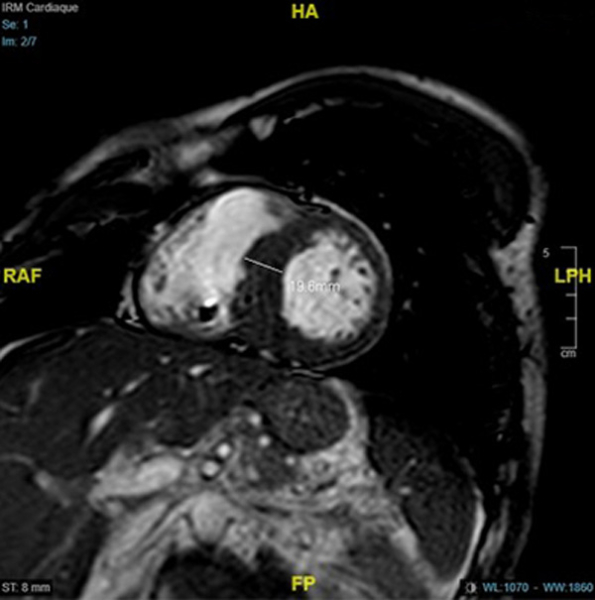

IRM

Figure 5

Figure 6

Figure 7

Figure 8 : Cartographie T1 N = 1000ms sur l’IRM 1,5 T

Conclusions de l’IRM :

- Cardiomyopathie hypertrophique asymétrique à prédominance septale (épaisseur maximale 19mm), sans atteinte VD

- Cinétique segmentaire homogène

- Zone de fibrose punctiforme inféro-septo-médiale isolée

- Absence d’allongement du T1